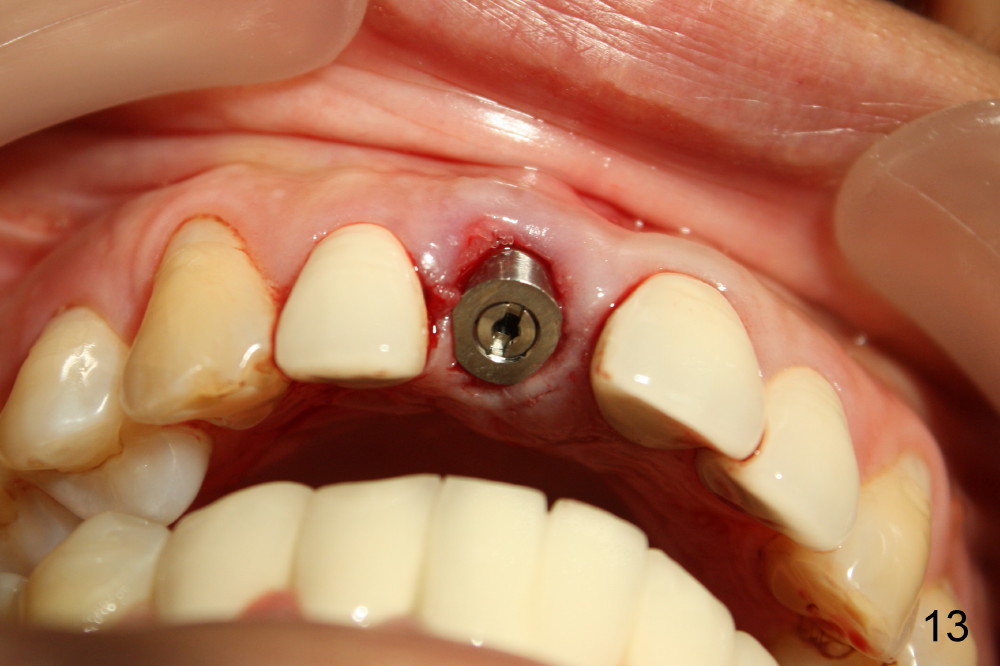

当我们拔出3.5毫米钻头(图五:最后一个钻头)时,就可以看见在舌侧骨板植牙洞型制备(图十一:圆圈)。图十二,图十三分别显示立刻植牙正面观和切缘观,植牙几乎占据所有牙槽窝空间,不需植骨或者缝线。植牙好像没有侵犯邻牙牙根(图十四,图十五,包括七号牙:侧切牙),其实只要熟悉局部解剖(图六至图十),即刻植牙反而容易进行。图十五虚线代表切牙孔,挺接近植牙(I),术后渗血较多,可能与此有关。除此之外,术后病人恢复很快。